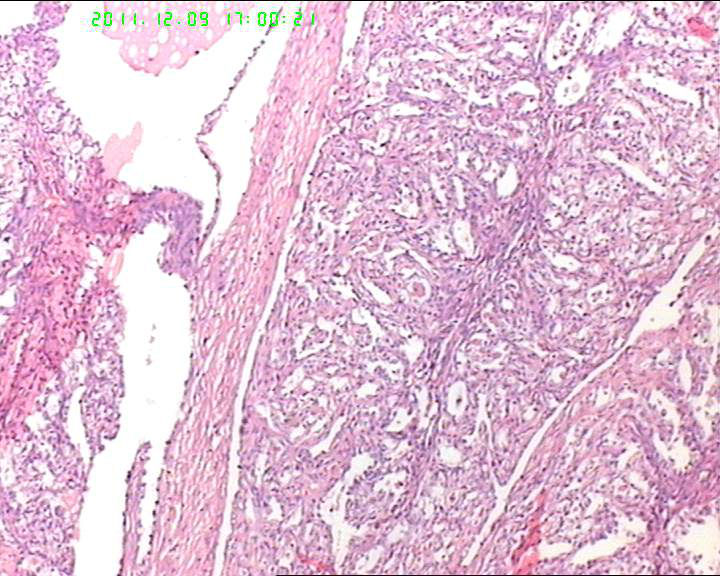

各位老师,会诊一下,49岁卵巢肿物,到底是什么呢?

盆腔包块4个月,13*8*7cm 大小,囊实性,实性区菜花状、灰白质脆,局部半透明。

有腺腔样结构,内衬靴钉样细胞,还可见透明细胞,首先考虑透明细胞癌,鉴别诊断:内胚窦瘤。内胚窦瘤的网状结构内衬是扁平的上皮。

肿瘤细胞弥漫性生长,细胞排列成腺样、腺泡状,细胞异型明显。突向腔内。

卵巢生殖细胞肿瘤,卵黄囊瘤;

性索间质肿瘤,颗粒细胞瘤;

转移性的癌